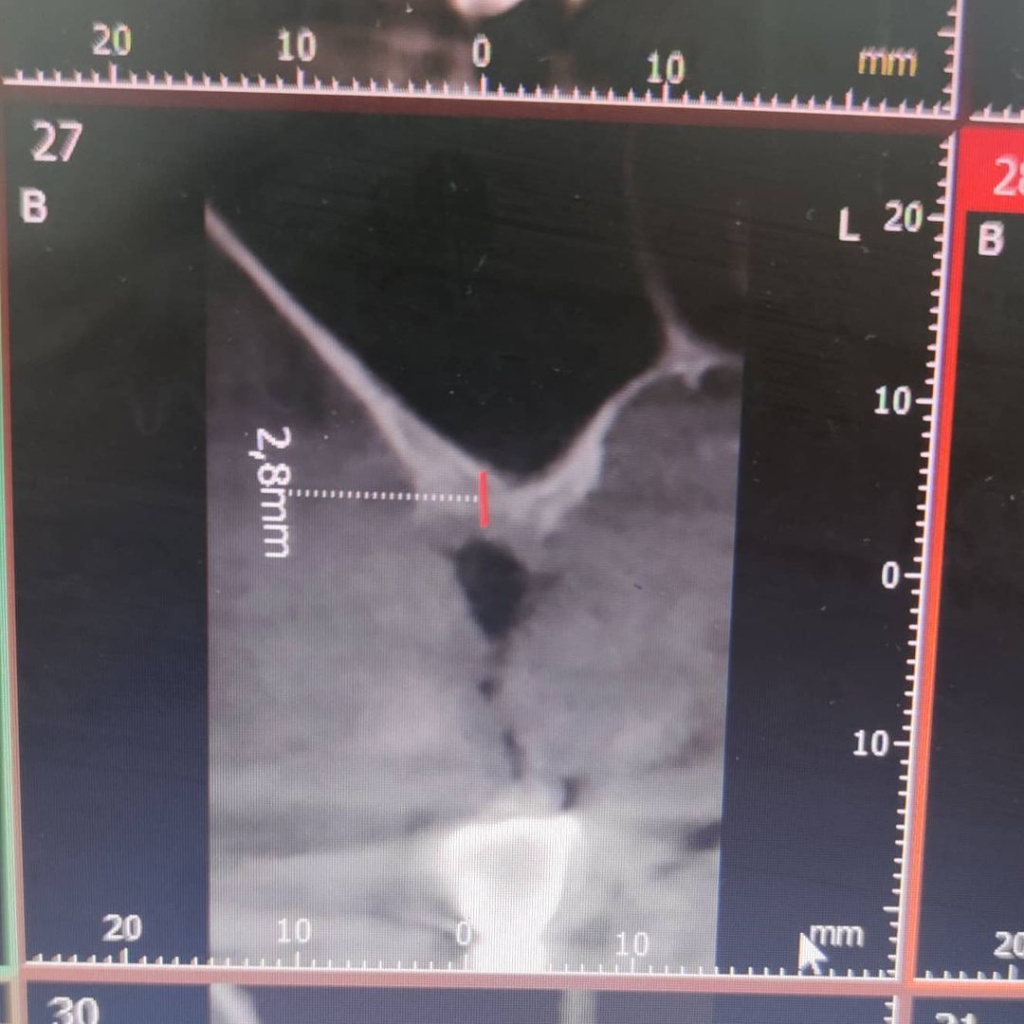

Площадь соприкосновения имплантата с костной тканью (BIC) является одним из основных факторов первичной стабилизации.

Чем больше площадь, тем больше стабильность!

Короткий имплантат с большой площадью поверхности будет также эффективен, как и длинный имплантат с той же площадью.